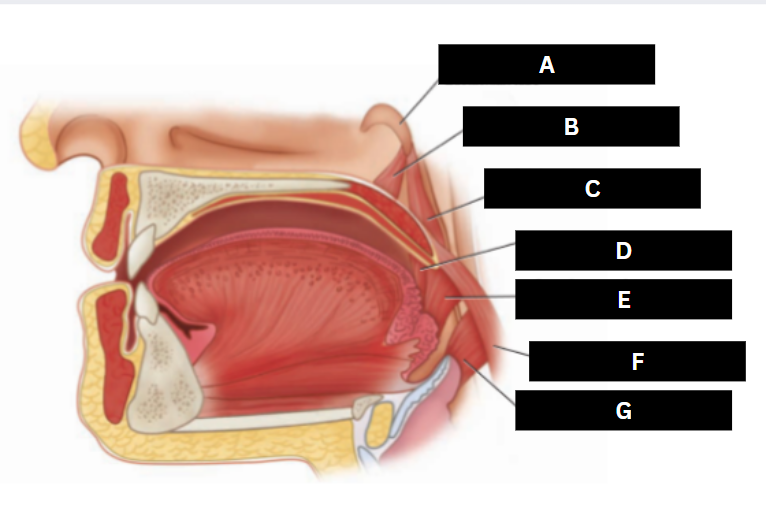

Eustachian tube

A

Levator veli palatini

B

Salpingopharyngeus

C

Palatoglossus

D

Superior pharyngeal constrictor

E

Palatopharyngeus

F

Middle pharyngeal constrictor

G